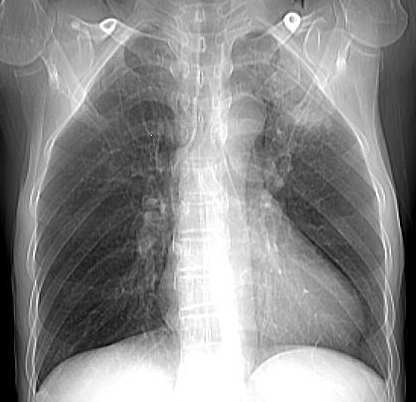

男,58岁,咳嗽1月加重1周,伴痰中带血

左肺上叶胸膜下不规则团块阴影,内见空泡,边缘光整,肺纵比率>50%,支持左肺癌的诊断。

ct:左上肺块状影、其内徐点状气体外蜜度大致均匀。周围粗大索状影

临床:59岁、瘘中带血

诊断1左上肺癌?2肺结核?建议痰检、穿刺活检

左上肺病灶与胸膜脂肪线存在,未见明显胸膜凹陷征,虽然病灶边缘不规则,但未见明显“短毛剌、切迹征、免耳征、血管束集征”,其间亦见条索状、斑点状影,认为左上肺结核或炎性病变>周围型肺癌。